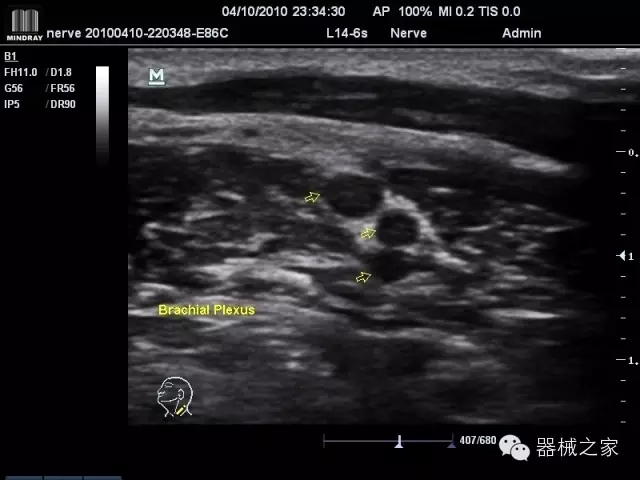

臨床圖片賞析